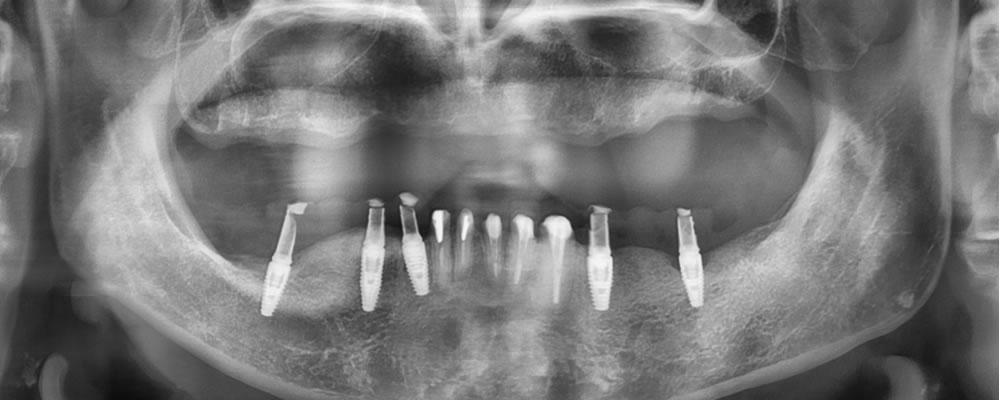

最終補綴物の装着

仮歯の状態で問題がないかを確認し、下顎臼歯部インプラントと下顎前歯部セラミッククラウンをセットしました。

治療を終え、口元の審美性が改善している事がわかります。

▼顔貌・レントゲン画像

すべての治療が終了し、「歯がボロボロで入れ歯ではうまく噛めない」という主訴が改善され、「ちゃんと噛める」「見た目も綺麗」な状態になって、ものすごく嬉しいという声を頂きました。